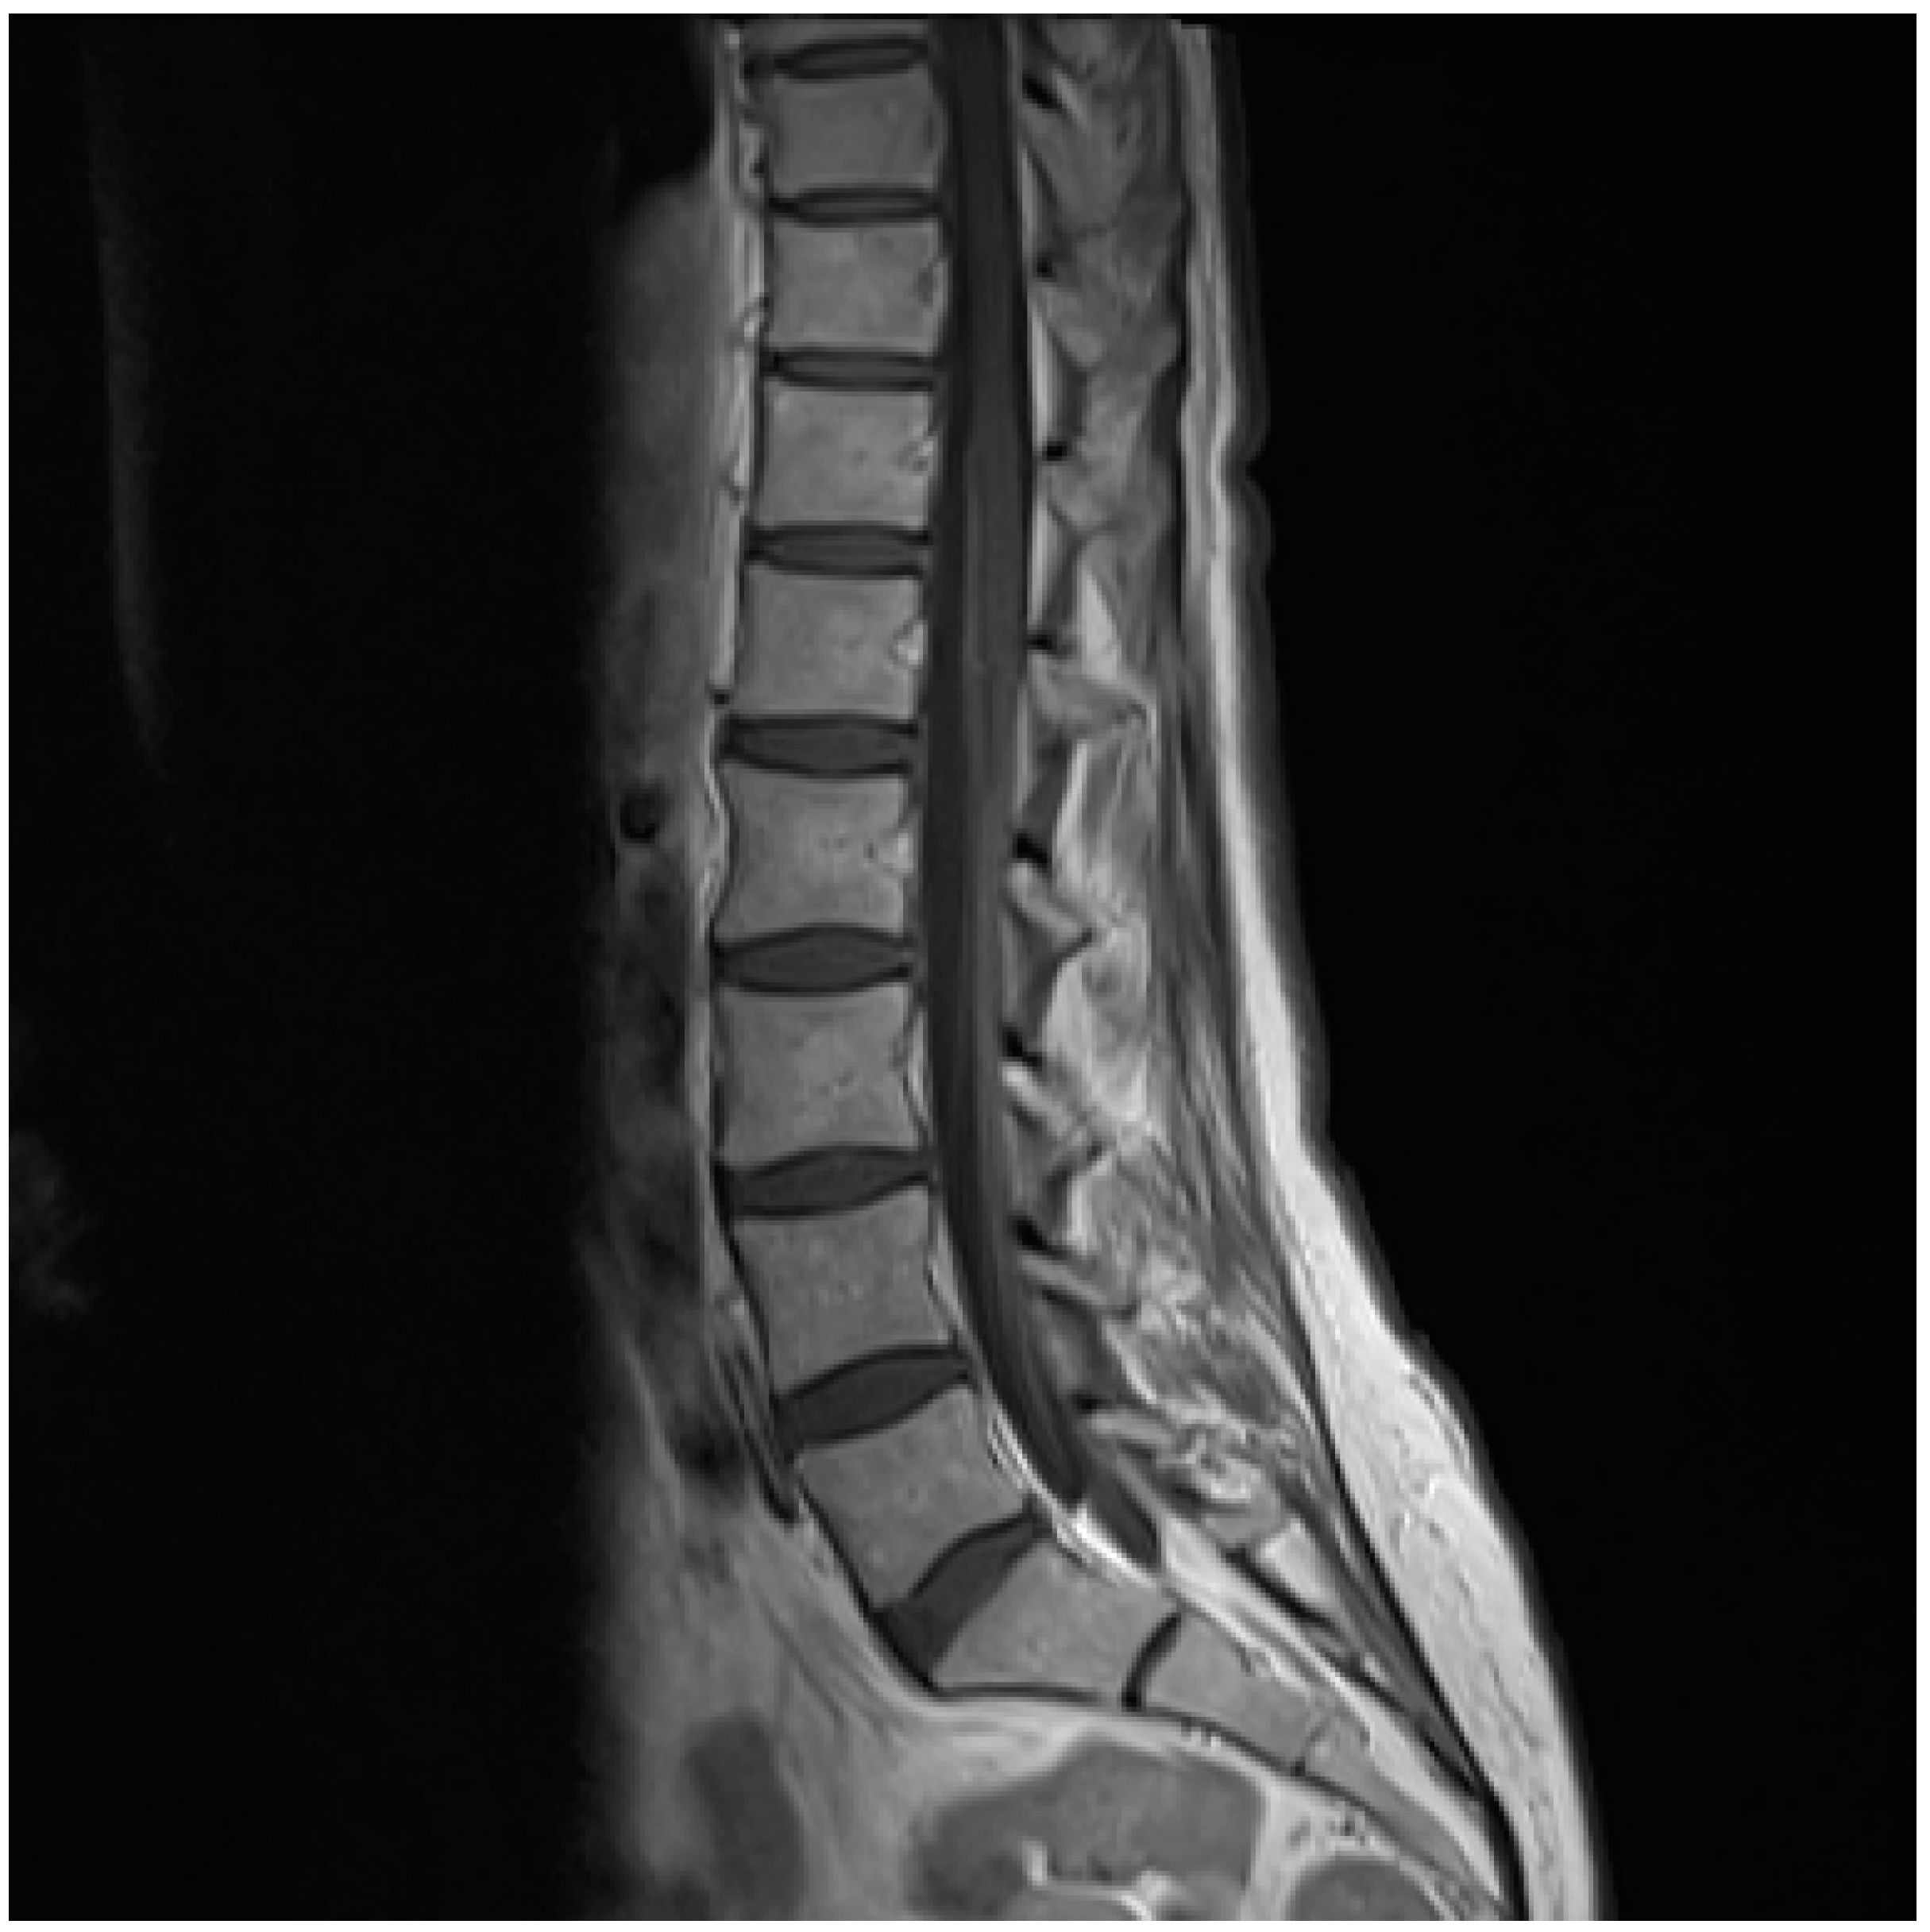

Lyme Neuroborreliosis in a Patient with Breast Cancer: MRI and PET/CT Findings

Abstract